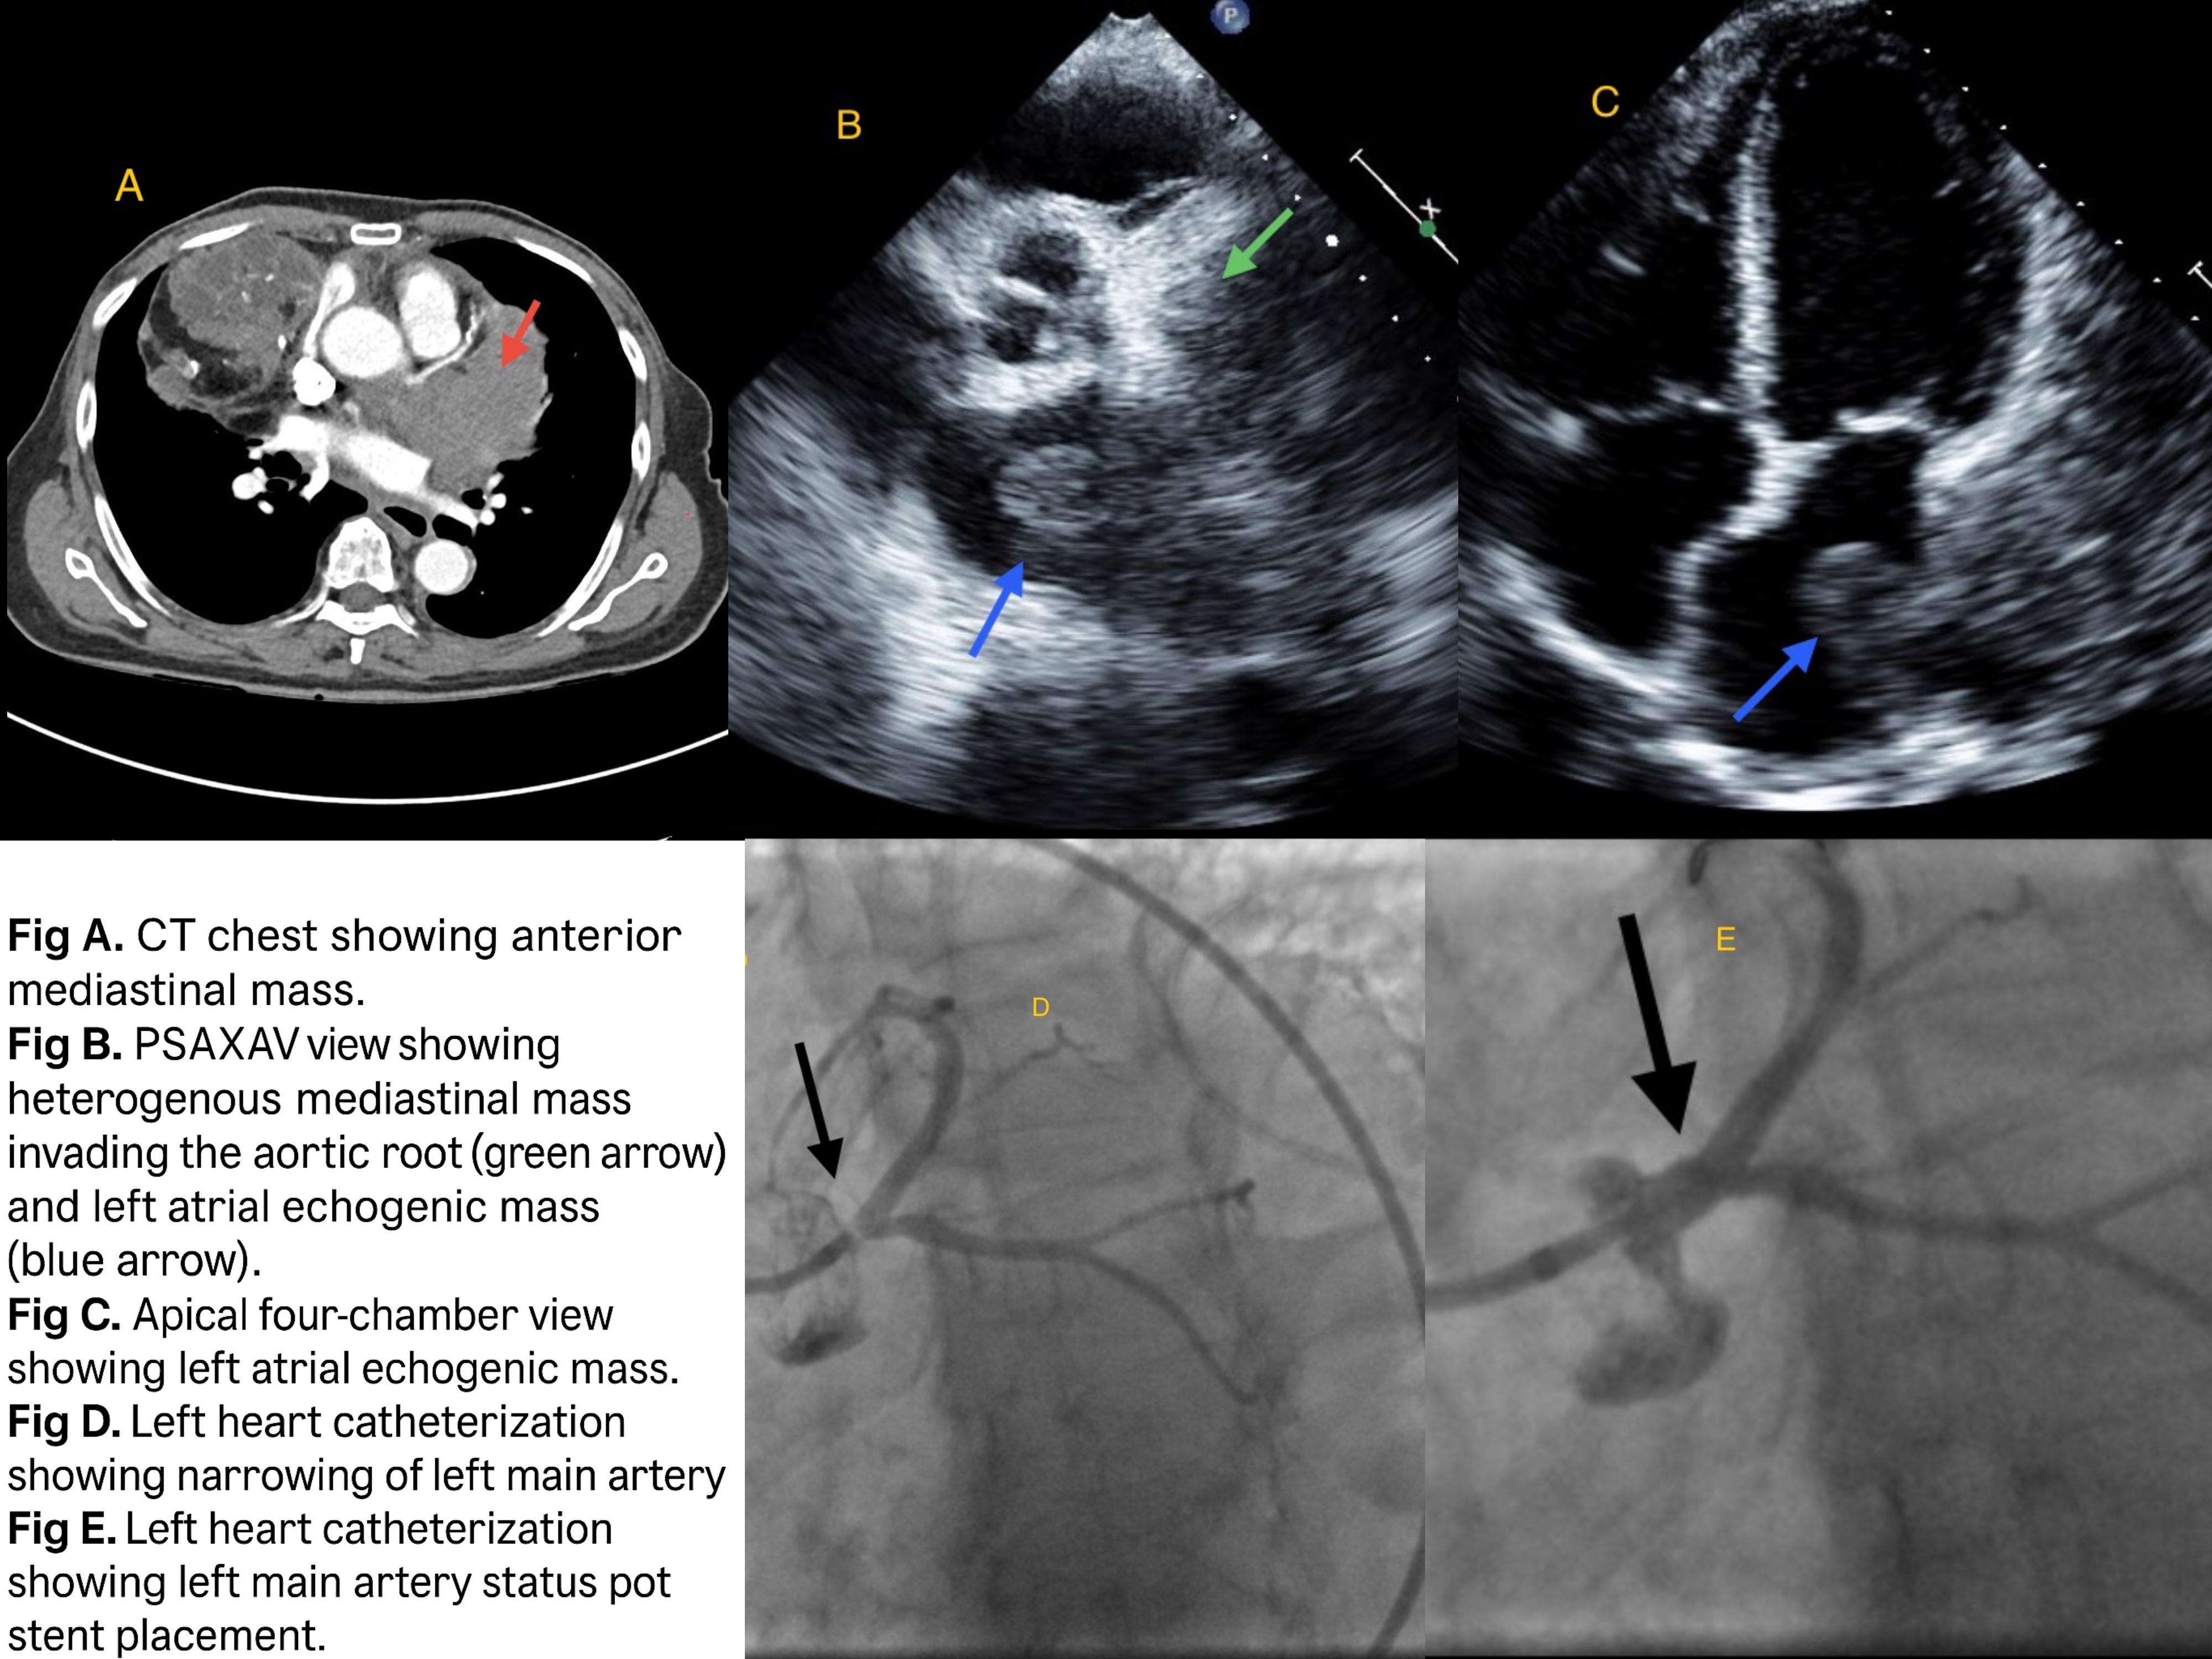

A 76-year-old female with a past medical history including HTN, DM, HLD, bilateral breast cancer (status post bilateral mastectomy and radiation), and prior thymoma presented with acute-onset dyspnea and chest pain. Initial evaluation revealed elevated troponin levels up to 9 ng/mL and sinus tachycardia with RBBB on ECG. CT chest demonstrated a large left anterior mediastinal mass infiltrating the pericardium, with suspected invasion into the left inferior pulmonary vein.Transthoracic echocardiography revealed a heterogeneous mediastinal mass invading the aortic root, causing extrinsic compression of the left main coronary artery, as well as involvement of the left superior pulmonary vein, left atrial lateral wall, and basal lateral left ventricular wall. A 2.1 x 2.1 cm echogenic mass was noted in the left atrial cavity. Initial coronary angiography revealed 75% narrowing of the left main coronary artery, but no intervention was performed. Surgical consultation with both cardiothoracic and thoracic surgery deemed the patient not a suitable candidate for resection or bypass due to extensive local invasion and overall frailty. A repeat angiogram one week later revealed progression to 90% left main stenosis, prompting an urgent high-risk PCI with successful stent placement.

Given rapid progression of left main coronary stenosis secondary to extrinsic tumor compression, and the patient’s inoperable status, a heart team approach led to the decision for high-risk PCI. The procedure was performed successfully, restoring perfusion and relieving symptoms.This case is an example of uncommon etiology of left main coronary artery compression from an invasive mediastinal tumor. When surgery was not feasible, PCI offered a successful alternative and served as a palliative measure when other options were not viable.